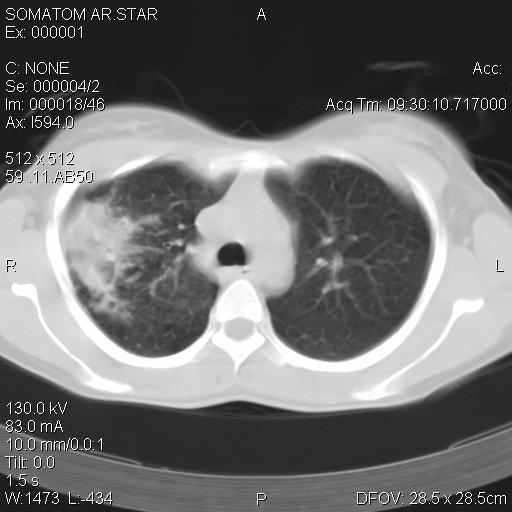

Рис. 6. Компьютерная томограмма органов грудной клетки больной С., 24 года в процессе лечения.

Однако при контрольном рентгенологическом исследовании органов грудной клетки от 25.03.2005 г. выявлено: в S1, S2, S3 правого легкого инфильтрация легочной ткани. На фоне инфильтрации крупные округлые очаги. В S2 полость распада. Умеренная перибронхиальная инфильтрация (Рис. 5). Компьютерная томография от 28.03.2005 г.: в верхней доле правого легкого инфильтрация с множественными полостями распада, очагами различной плотности. Слева в S4-S5 инфильтрация легочной ткани с мелкими полостями распада (рис. 6).

Компьютерная томография органов грудной клетки от 16.07.2005 г.: верхняя доля в гиповентиляции. Полостей распада не определяется. Инфильтрации и полостей распада в S4 и S5 левого легкого определяется (рис. 9). Пациентка выписана на амбулаторное лечение 13.07.2005 г.

Рис. 9. Компьютерная томограмма органов грудной клетки больной С., 24 года после клапанной бронхоблокации.